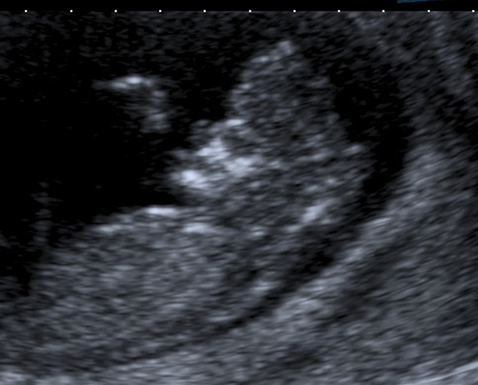

The anencephalic fetus demonstrates no clear frontal bone and often the facial bones may appear unusual also with the orbits appearing prominent – the so called 'frog-eyed appearance'. There may be some brain visible but this is variable. There is no bright skull vault covering the brain.

This image shows the facial view of an anencephalic fetus. Note the frog-eyed appearance. Also note that the skull vault is completely absent.